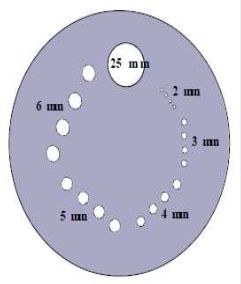

低對比偵測度

目的:測定電腦斷層掃描儀對低對比物體之分辨力。

‧測試所需設備:ACR測試假體(0.6%,6HU)或儀器廠商提供之類似設備,

其內含有低對比物體(小於等於1%,10 HU) 分辨力測試

模版製成之測試假體。

‧效能判定準則:常規成人腹部與常規成人頭部掃描模式下,最小可見之低對

比物直徑與基準值相較,其直徑增加不可超過1 mm 。

空間解析度

目的:測定電腦斷層掃描儀之空間解析度。

‧測試所需設備:ACRnCT測試假體或儀器廠商提供之類似設備。

‧效能判定準則:

常規成人腹部掃描模式應可清楚分辨5 lp/cm之區塊。

高解析度肺部掃描模式應可清楚分辨6 lp/cm之區塊。